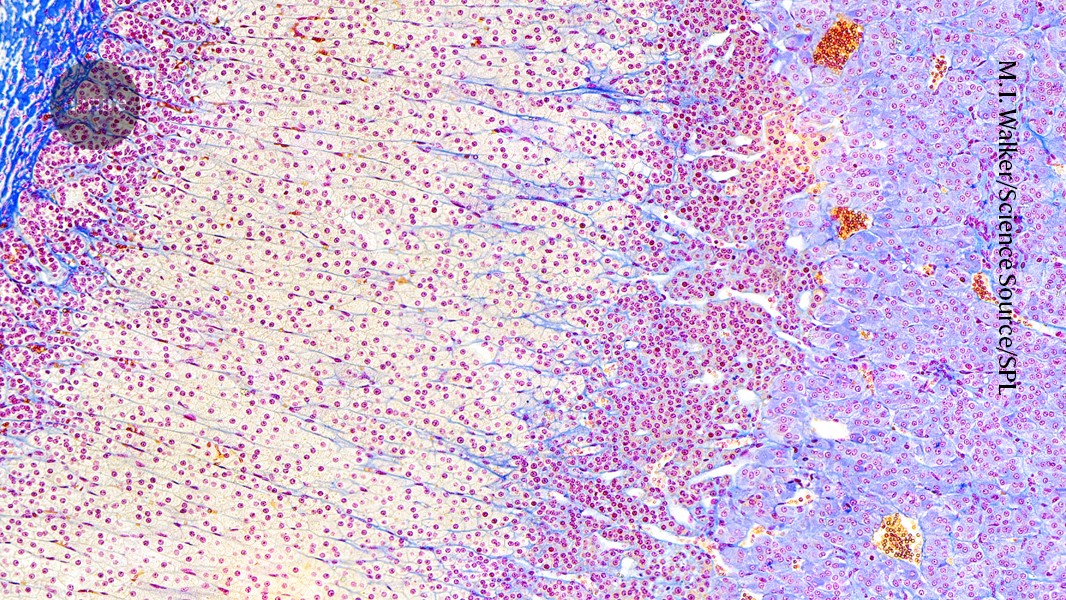

Share Facebook Twitter LinkedIn Pinterest Email Copy Link RESEARCH HIGHLIGHT 21 October 2025 Lab-grown structure mimics the adrenal cortex, which produces the critical hormone called cortisol. Glandinadish hormone Real secretes Stress